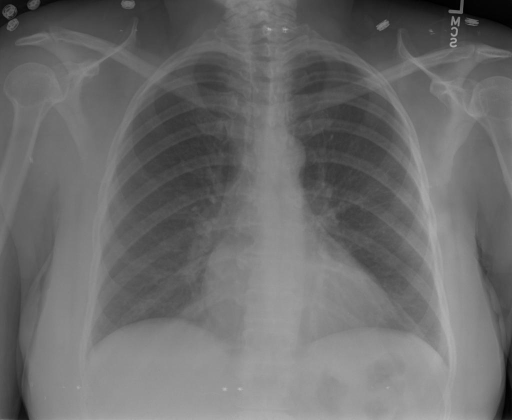

# 本文贡献 ![](./assets/images/xrayglm.png) - 借助ChatGPT以及公开的数据集,我们构造了一个`X光影像-诊断报告`对的医学多模态数据集; - 我们将构建的中文胸部X光片诊断数据集在[VisualGLM-6B](https://github.com/THUDM/VisualGLM-6B)进行微调训练,并开放了部分训练权重用于学术研究; # 数据集 - [MIMIC-CXR](https://physionet.org/content/mimic-cxr-jpg/2.0.0/)是一个公开可用的胸部X光片数据集,包括377,110张图像和227,827个相关报告。 - [OpenI](https://openi.nlm.nih.gov/faq#collection)是一个来自印第安纳大学医院的胸部X光片数据集,包括6,459张图像和3,955个报告。 在上述工作中,报告信息都为非结构化的,不利于科学研究。为了生成合理的医学报告,我们对两个数据集进行了预处理,并最终得到了可以用于训练的**英文报告**。除此之外,为了更好的支持中文社区发展,借助ChatGPT的能力,我们将英文报告进行了中文翻译,并最终形成了可用于训练的数据集。 |数据集|数量|下载链接| |:-|:-|:-| |MIMIC-CXR-zh|-|-| |OpenI-zh|6,423|[诊疗报告](./data/Xray/openi-zh.json) 、[X光影像](https://pan.baidu.com/s/13GBsDMKf6xBZBSHpoWH_EA?pwd=k9sh)| # 快速上手 1. 安装环境 ```bash # 安装依赖 pip install -r requirements.txt # 国内换源安装依赖 pip install -i https://mirrors.aliyun.com/pypi/simple/ -r requirements.txt ``` 此时默认会安装`deepspeed`库(支持`sat`库训练),此库对于模型推理并非必要,同时部分`Windows`环境安装此库时会遇到问题。 如果想绕过`deepspeed`安装,我们可以将命令改为: ```bash # 安装依赖 pip install -i https://mirrors.aliyun.com/pypi/simple/ -r requirements_wo_ds.txt # 安装SwissArmyTransformer pip install -i https://mirrors.aliyun.com/pypi/simple/ --no-deps "SwissArmyTransformer>=0.3.6" ``` 2. 模型推理 CLI推理: ```python python cli_demo.py --from_pretrained checkpoints/finetune-XrayGLM-05-25-01-04 --prompt_zh '详细描述这张胸部X光片的诊断结果' ``` 更多[参数](https://github.com/WangRongsheng/XrayGLM/blob/main/cli_demo.py#L16) # 效果展示 诊断: |X光影像|诊疗报告(医生)|XrayGLM| |:-|:-|:-| |![](./data/Xray/2_1.png)|根据X射线图像,心脏大小正常,肺部看起来很清晰。已经排除了肺炎、积液、水肿、气胸、腺病、结节或肿块的存在。该发现表明一切正常。换句话说,总体印象是胸部正常。|X光片显示,心脏大小正常。肺部没有气胸或胸腔积液的证据。骨骼结构看起来没有任何异常。总的来说,X光片表明没有发现急性心肺疾病的迹象。| |![](./data/Xray/2882_1.png)|X光图片显示没有扭曲的区域、可疑的骨质不透明度或胸腺积液。心脏大小轻微增大,但非常稳定。此外,没有气胸的证据,肺野也正常。总体来说,X光片显示没有急性心脏异常,但要注意轻微的心脏扩大。|X光片显示,心脏大小正常。肺部和纵隔轮廓清晰,没有气胸或胸腔积液的证据。骨骼结构完整,没有任何急性异常。| |![](./data/Xray/2577_1.png)|心影形态在正常范围内。没有急性骨质异常。有可能出现没有明显的吸水或肺实质状况的线索。没有大面积积液或气胸。有可能怀疑其有误吸或肺实质问题。为了确诊和治疗,可能需要进行适当的影像学随访。|心脏大小正常,肺部和纵隔轮廓清晰。没有急性异常或活动受限的证据。没有任何明显的气胸、胸腔积液或肺不张的迹象。此外,也没有发现任何局灶性骨质异常或其他急性疾病。| 多轮对话: |X光影像|诊疗报告(医生)| |:-|:-| |![](./data/Xray/861_1.png)|右侧主动脉突出观察到。心脏大小正常。胸部未发现明显的肺气肿、胸膜积液或可疑的肺部病变。报告指出已知右侧主动脉情况正常。| ```bash >> X光影像路径:./data/Xray/861_1.png >> 用户:这是一张什么图? >> XrayGLM:这张图片显示的是一张肺部检查的X光片。 >> 用户:请描述这张胸部X光片的诊断结果 >> XrayGLM:心脏大小正常,肺部清晰。没有急性心肺疾病的证据。 >> 用户:是否存在肺气肿? >> XrayGLM:没有肺气肿。心脏大小正常,肺部清晰。没有发现急性心肺疾病的证据。 >> 用户:平时饮食该注意什么? >> XrayGLM:饮食应该健康,均衡。建议增加蛋白质的摄入量,因为蛋白质有助于维持肌肉和骨骼的健康。多食用蔬菜、水果、全谷物以及健康的脂肪来源如橄榄油、鱼类等可以帮助获得足够的维生素和矿物质。此外,避免过度饮酒或吸烟,这些习惯可能会对心脏健康产生负面影响。 ``` # 项目致谢 1. [VisualGLM-6B](https://github.com/THUDM/VisualGLM-6B)为我们提供了基础的代码参考和实现; 2. [MiniGPT-4](https://github.com/Vision-CAIR/MiniGPT-4)为我们这个项目提供了研发思路; 3. ChatGPT生成了高质量的中文版X光检查报告以支持XrayGLM训练; 4. [gpt_academic](https://github.com/binary-husky/gpt_academic)为文档翻译提供了多线程加速; 5. [MedCLIP](https://github.com/RyanWangZf/MedCLIP) 、[BLIP2](https://huggingface.co/docs/transformers/main/model_doc/blip-2) 、[XrayGPT](https://github.com/mbzuai-oryx/XrayGPT) 等工作也有重大的参考意义; ![](./assets/images/mpu.png) 这项工作由[澳门理工大学应用科学学院](https://www.mpu.edu.mo/esca/zh/index.php)硕士生[王荣胜](https://github.com/WangRongsheng) 、[段耀菲](https://github.com/IsBaSO4) 、[李俊蓉](https://github.com/lijunrong0815)完成,指导老师为檀韬副教授、[彭祥佑](http://www.patrickpang.net/)老师。 *特别鸣谢:[USTC-PhD Yongle Luo](https://github.com/kaixindelele) 提供了有3000美金的OpenAI账号,帮助我们完成大量的X光报告翻译工作 # 免责声明 本项目相关资源仅供学术研究之用,严禁用于商业用途。使用涉及第三方代码的部分时,请严格遵循相应的开源协议。模型生成的内容受模型计算、随机性和量化精度损失等因素影响,本项目无法对其准确性作出保证。即使本项目模型输出符合医学事实,也不能被用作实际医学诊断的依据。对于模型输出的任何内容,本项目不承担任何法律责任,亦不对因使用相关资源和输出结果而可能产生的任何损失承担责任。 # 项目引用 如果你使用了本项目的模型,数据或者代码,请声明引用: ```bash @misc{wang2023XrayGLM, title={XrayGLM: The first Chinese Medical Multimodal Model that Chest Radiographs Summarization}, author={Rongsheng Wang, Yaofei Duan, Junrong Li, Patrick Pang and Tao Tan}, year={2023}, publisher = {GitHub}, journal = {GitHub repository}, howpublished = {\url{https://github.com/WangRongsheng/XrayGLM}}, } ``` # 使用许可 此存储库遵循[CC BY-NC-SA](https://creativecommons.org/licenses/by-nc-sa/4.0/) ,请参阅许可条款。